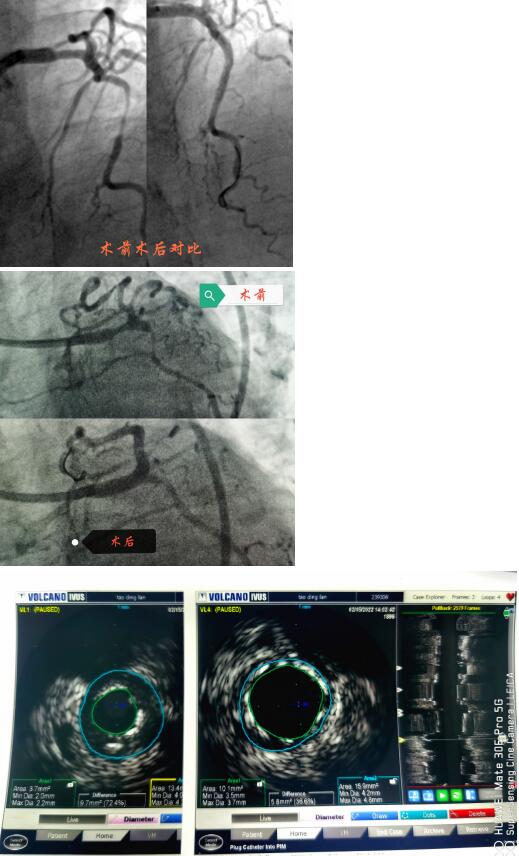

春節(jié)剛過,陶奶奶的孩子們帶著陶奶奶再次來到了江寧中醫(yī)院心內(nèi)科準(zhǔn)備拆除這顆潛在的“致命炸彈”。韋鋒主任反復(fù)研究陶奶奶的前期手術(shù)影像,心中擬定著多個手術(shù)方案。經(jīng)過充分準(zhǔn)備,2月15日,韋鋒主任再次為陶奶奶進(jìn)行了介入手術(shù)。術(shù)中通過血管內(nèi)超聲(IVUS)精細(xì)、準(zhǔn)確評估陶奶奶的冠脈病變情況,發(fā)現(xiàn)陶奶奶的左主干最小管腔面積僅僅3.7mm2,;前降支近段全程鈣化,最嚴(yán)重處呈270度的環(huán)形鈣化,最小管腔面積僅僅2.1mm2;回旋支開口正常,回旋支近端最小管腔面積1.8mm2。韋鋒主任根據(jù)IVUS的結(jié)果,改變了原來擬定的DKCRUSH術(shù)式,決定采用藥物球囊和藥物涂層支架相結(jié)合的方式處理病變(LCX藥物球囊,LM-LAD植入支架),經(jīng)過近2個小時的手術(shù),陶奶奶的冠脈血管又“完美”地回來了。

韋鋒主任術(shù)中在仔細(xì)研究陶奶奶的IVUS結(jié)果,指導(dǎo)手術(shù)更精確的進(jìn)行。

據(jù)韋鋒主任介紹,上世紀(jì)八十年代,類似陶奶奶的這種累及左主干的多支病變,曾被視為內(nèi)科微創(chuàng)介入的禁忌,隨著心內(nèi)科微創(chuàng)介入技術(shù)的發(fā)展和支架的更新?lián)Q代,目前,這類病變可以在有豐富介入經(jīng)驗的介入醫(yī)生面前“迎刃而解”,不再是那么的可怕。近幾年隨著IVUS、OCT等腔內(nèi)影像學(xué)的發(fā)展,這類病變可以更精準(zhǔn)的進(jìn)行治療。比如陶奶奶這個情況,在IVUS指導(dǎo)下,可以精確測量左主干的狹窄程度和長度,指導(dǎo)支架的選擇;準(zhǔn)確評價左主干的解剖形態(tài)及病變性質(zhì),結(jié)合分叉處各分支開口的病變情況,制定更優(yōu)更個體化的介入治療策略,并且評價支架置入后的效果優(yōu)化支架置入的過程,整體改善患者遠(yuǎn)期預(yù)后。